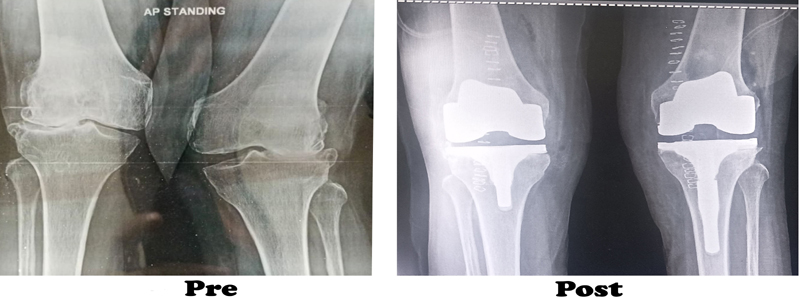

During the knee replacement surgery, the worn out surface (cartilage) of the joint is removed and is capped with implants called as endo-prosthesis. The femur and tibial sides are metal backed and in between there is polyethylene ‘insert’. The patella may or may not be replaced, depending upon the surgeon preference and condition of patellar cartilage.

The surgeon will make an incision on the top of your knee in order to expose the damaged area of your joint. The standard incision size can be as long as 10 inches, but a minimally invasive procedure can result in incisions as short as 6 inches. During the operation, the surgeon moves your kneecap aside and cuts away damaged bone and cartilage, which are then replaced with new metal and plastic components. The components combine to form a synthetic (but biologically compatible) joint that mimics the movement of your natural knee. Most knee replacement procedures take 30min - 1 hour to complete.